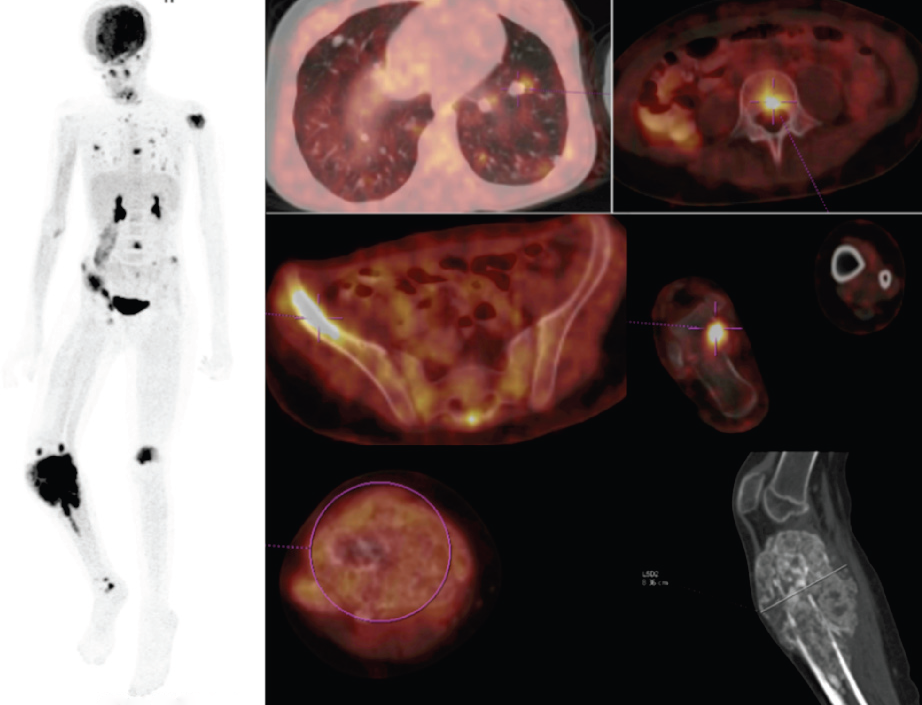

Pozitron Emisyon Tomografi–Bilgisayarlı Tomografi (PET-BT)

PET-BT çekimi öncesinde radyoaktif madde damar yoluyla enjekte edilerek sistemik dağılımı beklenir, ardından bu maddenin dokunun metabolik aktivitesine göre vücuttaki birikimi ölçümlenir. Elde edilen bilgiler üç boyutlu halde görüntülenir. Hibrit görüntülenme tekniği kullanılarak bu bilgi BT ile birleştirdiğinde elde olunan görüntüler ile tümör hücrelerinin iyi ya da kötü ayrımında, tümörün kemoterapiye yanıtını değerlendirmede ve metastatik odak araştırılmasında bilgi elde olunur.

PET-BT ile damar yoluyla verilen radyoaktif maddenin dokuların metabolik

aktivitesine göre vücuttaki birikimi ölçümlenir.